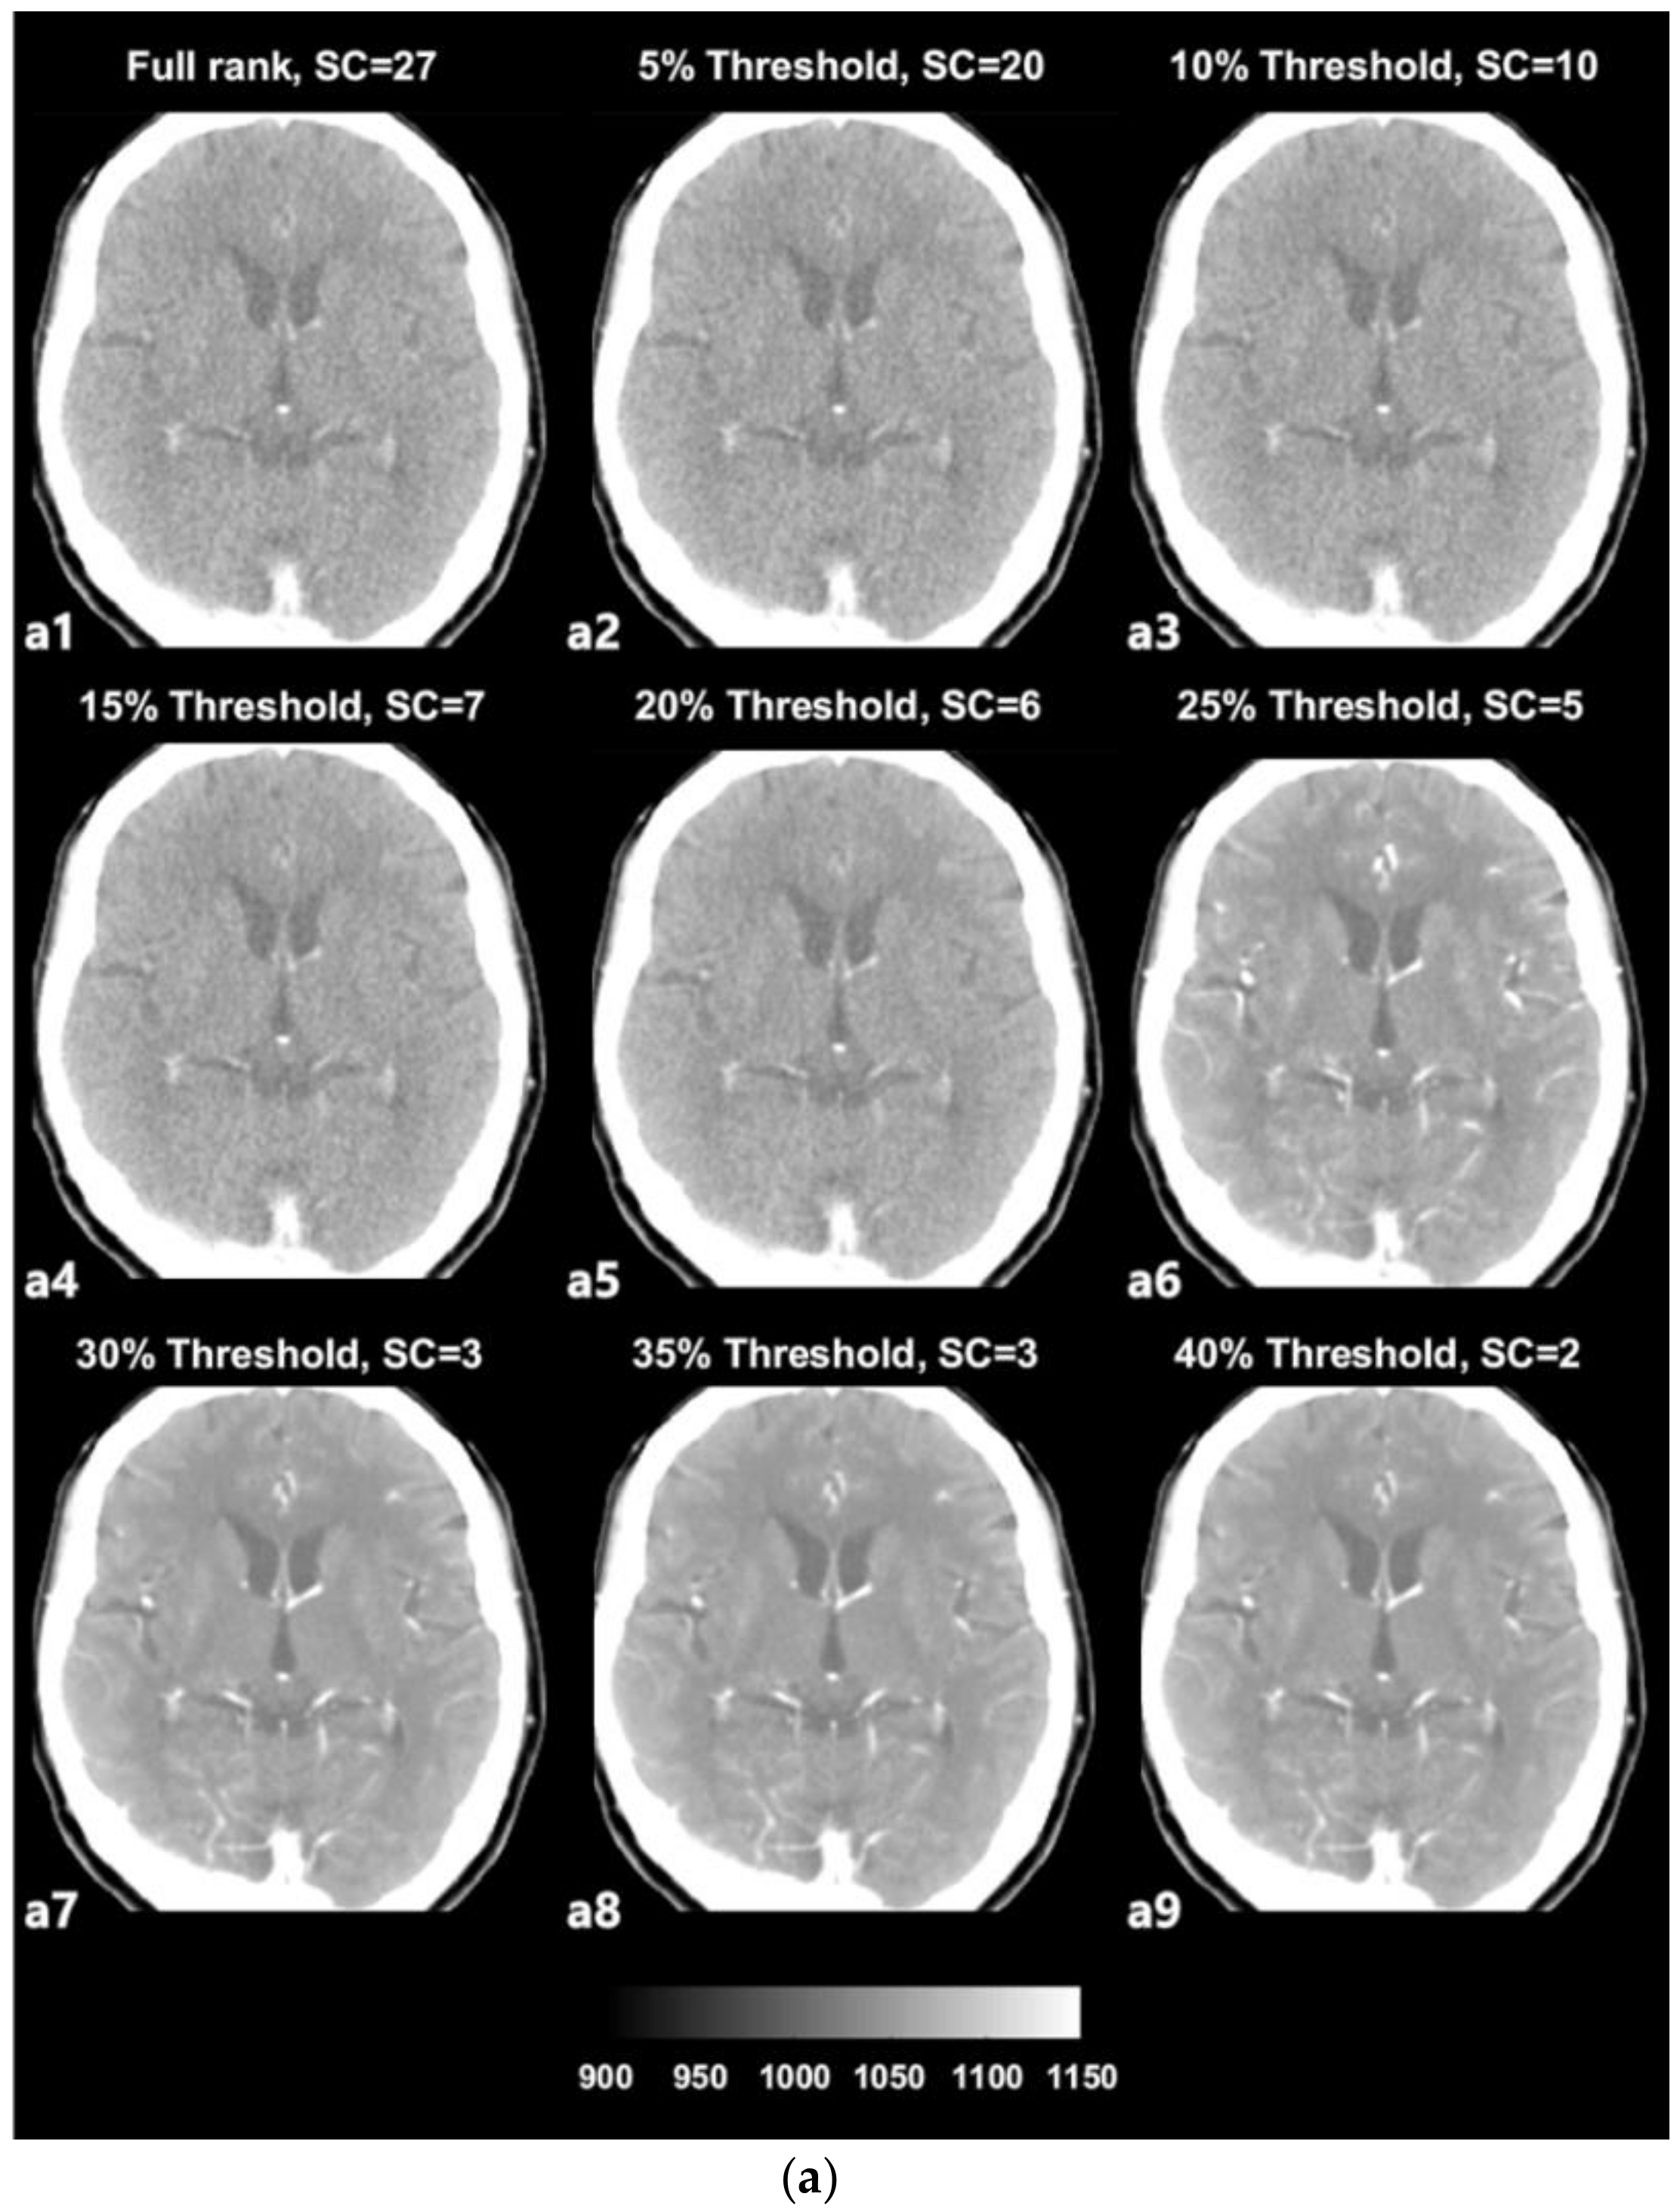

3.1. SVD-Based Noise Removal